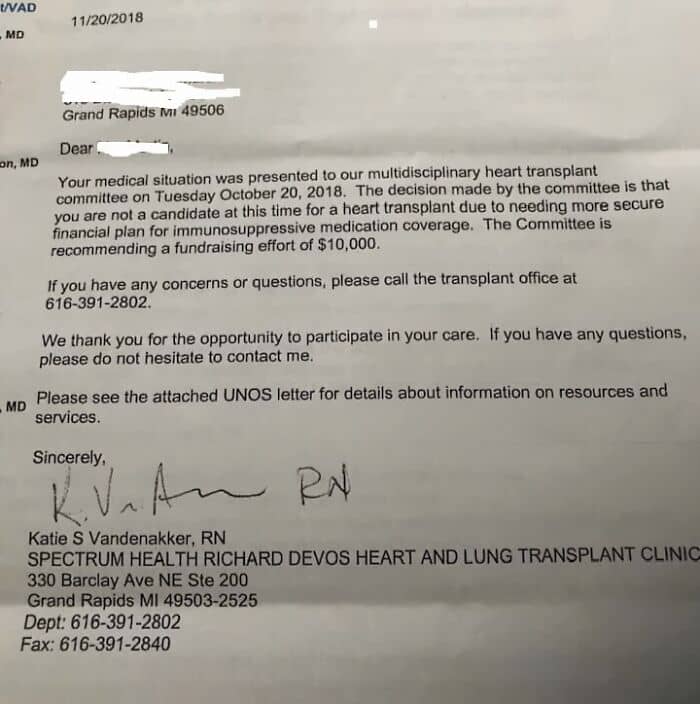

#55 The American Healthcare System, Not Rich Enough To Live